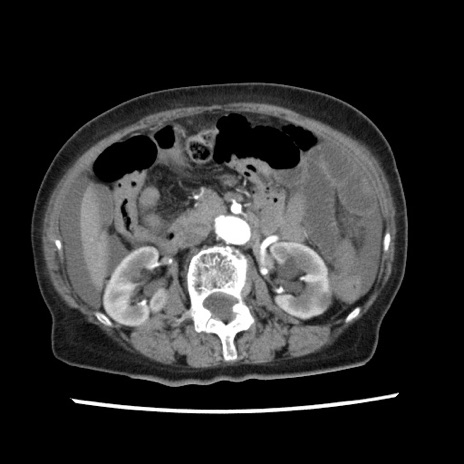

症例1(横断像)

【症例】80歳代女性

【主訴】腹痛

【現病歴】8時間前から腹痛あり来院。

【既往歴】糖尿病、脂質異常症、子宮体癌にて子宮全摘術

【身体所見】意識清明・会話良好だが腹痛で苦悶様、全腹部にわたって反跳痛と圧痛あり

【データ】WBC 13600、CRP 0.14、LDH 224、CK 90